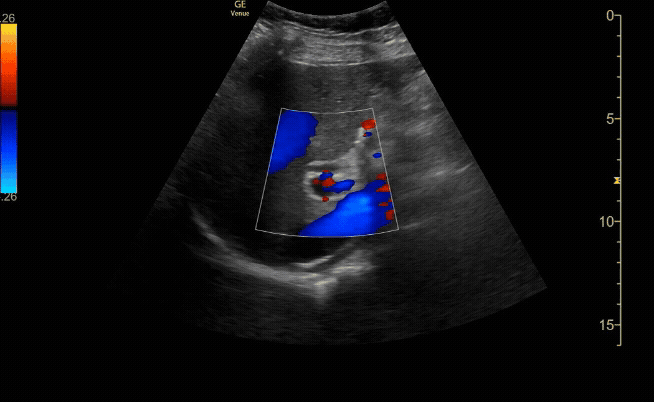

Common bile duct (if visualized) measuring <0.6cm with color flow seen in the portal vein.

c/o Jose Reyes, MD

Common bile duct tips

Doppler can be used to differentiate the CBD from the hepatic artery